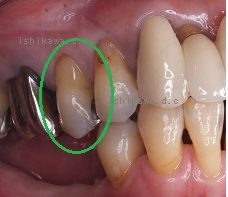

隣接面齲蝕 森本歯科医院